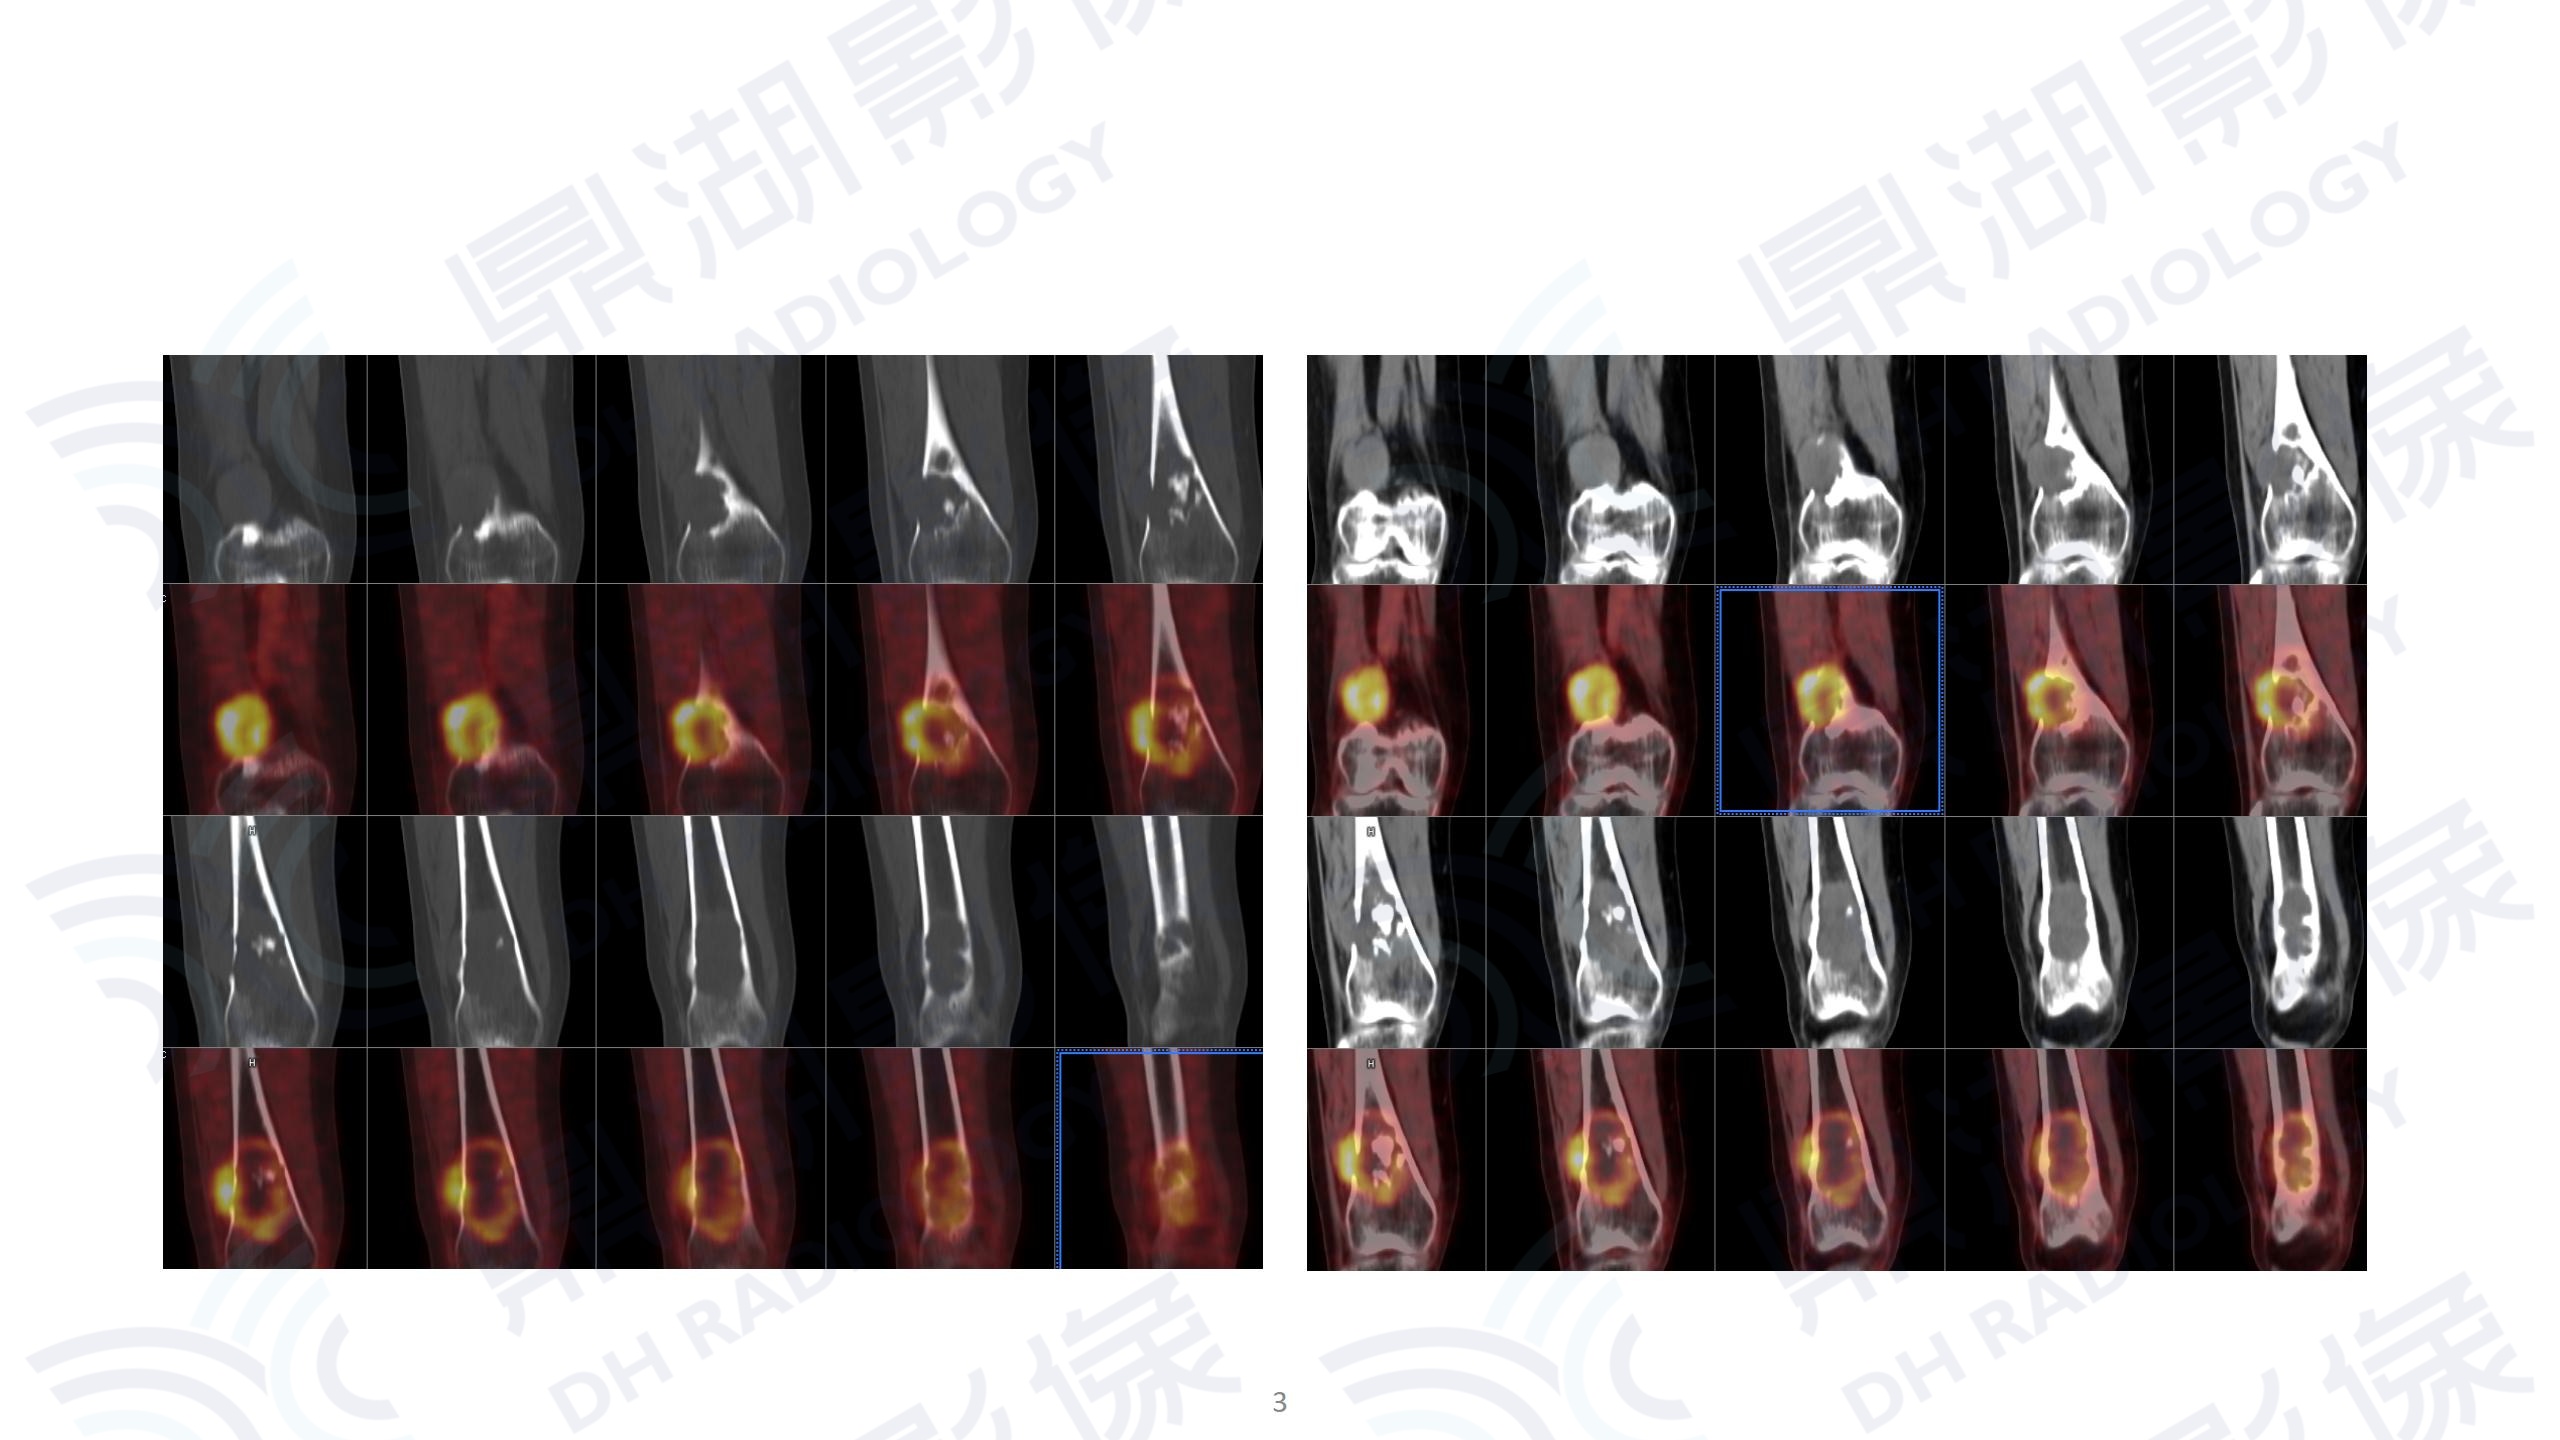

右股骨下段骨肉瘤

主诉: 右腿疼痛进行性加重1周。

右腿疼痛进行性加重1周。

外院MR提示右股骨下段占位,MT可能大。